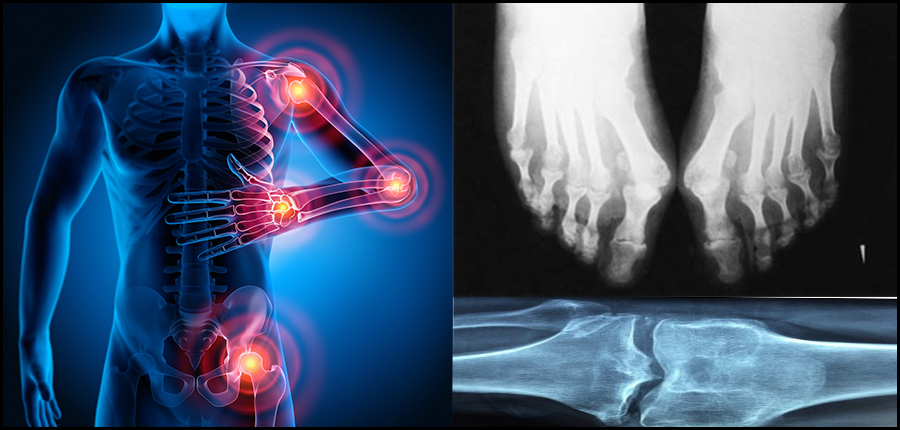

L’imagerie médicale (Echographie, clichés radiologiques…) est un outil de diagnostic et traitement indispensable dans les maladies rhumatismales et apporte un confort pour les malades.